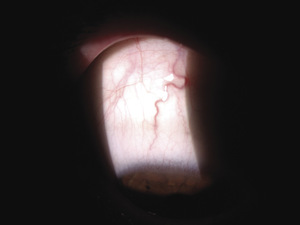

Rycina 4. Zamknięcie gałązki skroniowej dolnej tętnicy środkowej siatkówki z towarzyszącą ischemią siatkówki